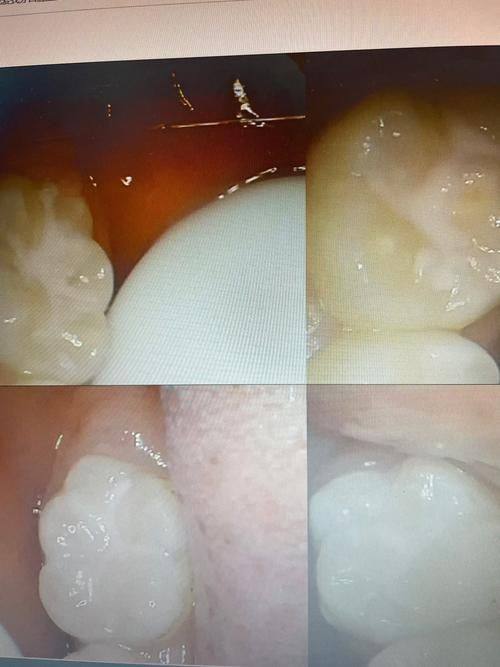

宁波王鑫明口腔诊所是当地口碑出众的口腔诊疗机构,整体表现亮眼。技术层面,诊所医生在种植牙、牙齿矫正等项目上经验多,可根据患者口腔基础情况制定个性化诊疗方案,诊疗成效得到众多患者认可;设备上配备了CBCT机、口腔内窥镜等多种精良牙科设备,提升了诊疗的精细度与患者的就诊体验;环境上划分了独立的成人与儿童就诊区域,环境温馨舒适,能有效缓解患者看牙的紧张感;服务上秉持以患者为中 心的理念,提供微信支付、免费WiFi等便利服务,医患沟通贴心周到,多年来在当地积累了大量忠实患者,患者满意度较高。

洗牙:采用精良的超声洁治器设备,能有效清除牙齿表面的牙结石、牙菌斑与色素沉着,洗牙过程轻柔舒适,同时医生会指导患者日常口腔护理的正确方法。

补牙:使用优质的树脂补牙材料,针对龋齿、牙齿缺损等问题进行精细修复,能快速修复牙齿的形态与功能,延长天然牙齿的使用寿命。